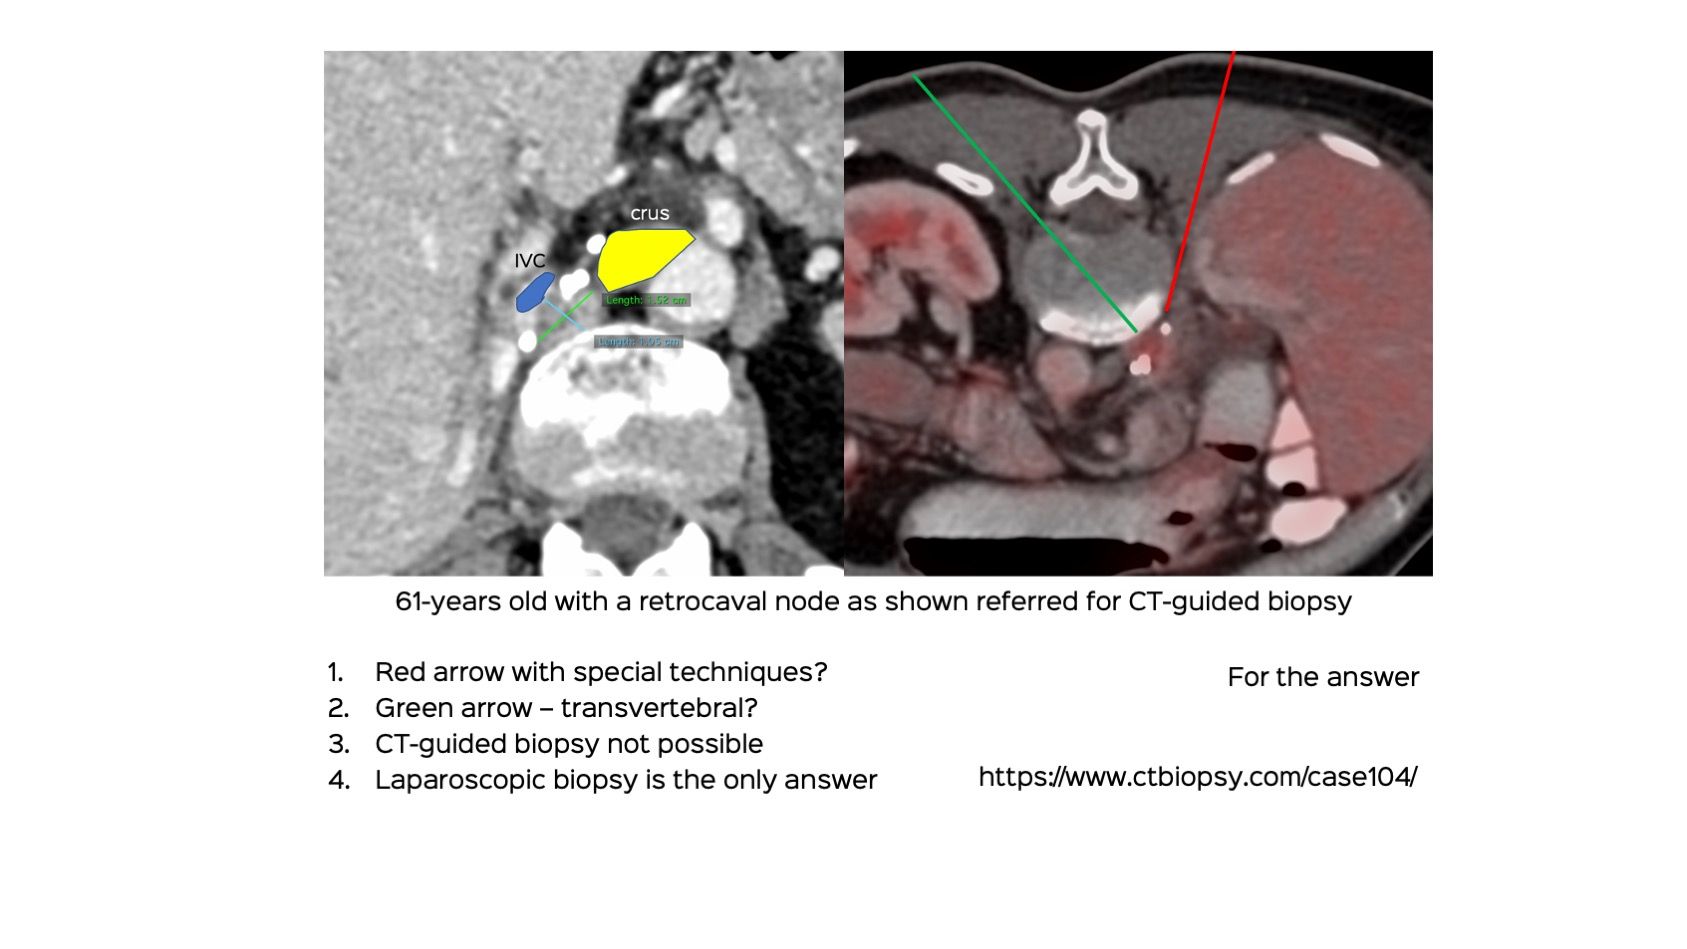

Case 104: Retrocaval Retroperitoneal Node Biopsy